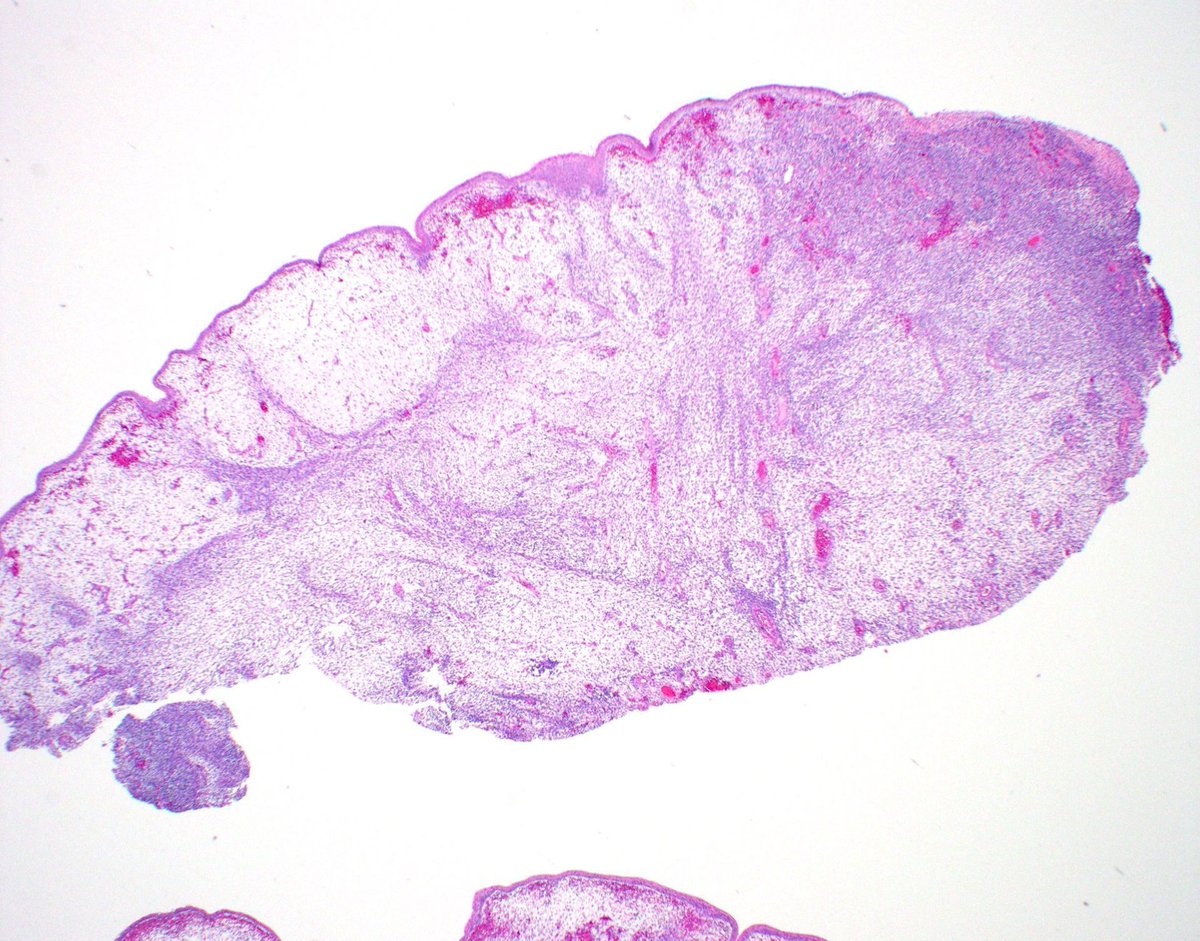

Polypoid vaginal mass from a young girl. Your diagnosis? More pics https://t.co/DaWIpwic4N Immunostains 🔬 https://t.co/EAiO8vGSkt Answer ✅ https://t.co/czXR6VkiRs #BSTpath #pathologists #pathology #pathTwitter #gynpath #pedipath